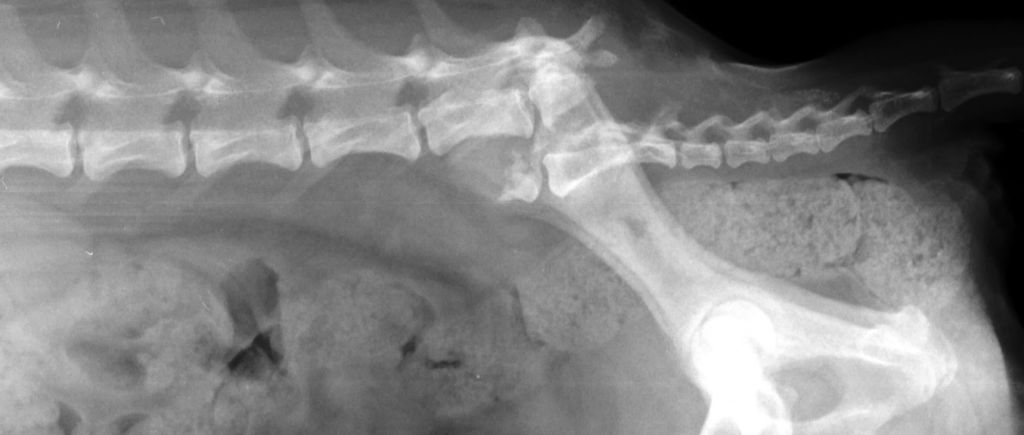

Рентген — отказ задних конечностей у собаки

При подозрении на спинальную патологию, проводиться тесты сохранности тактильной и болевой чувствительности в тазовых конечностях. Также необходимо оценить наличие рефлексов, болевых ощущений в позвоночном столбе. Назначаются также ультразвуковое и рентгенологическое исследование, позволяющие визуализировать патологические процессы.